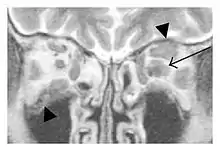

The extent of inflammation that can occur in IgG4-ROD is well demonstrated on magnetic resonance imaging (MRI).

Infraorbital nerve enlargement (IONE) is considered to be a particularly suspicious sign of IgG4-ROD, but seems to occur only when inflammation is in direct contact with the infraorbital canal.[10] IONE is defined as the infraorbital nerve diameter being greater than the optic nerve diameter in the coronal plane.

Swelling of the left superior and lateral rectus muscles, a mass lesion around the left optic disc (arrow), and enlargements of the left supraorbital nerve and the right infraorbital nerve (arrow heads) in a 60-year-old man with a serum IgG4 of 463 mg/dL.[1] (T1-weighted MRI) |